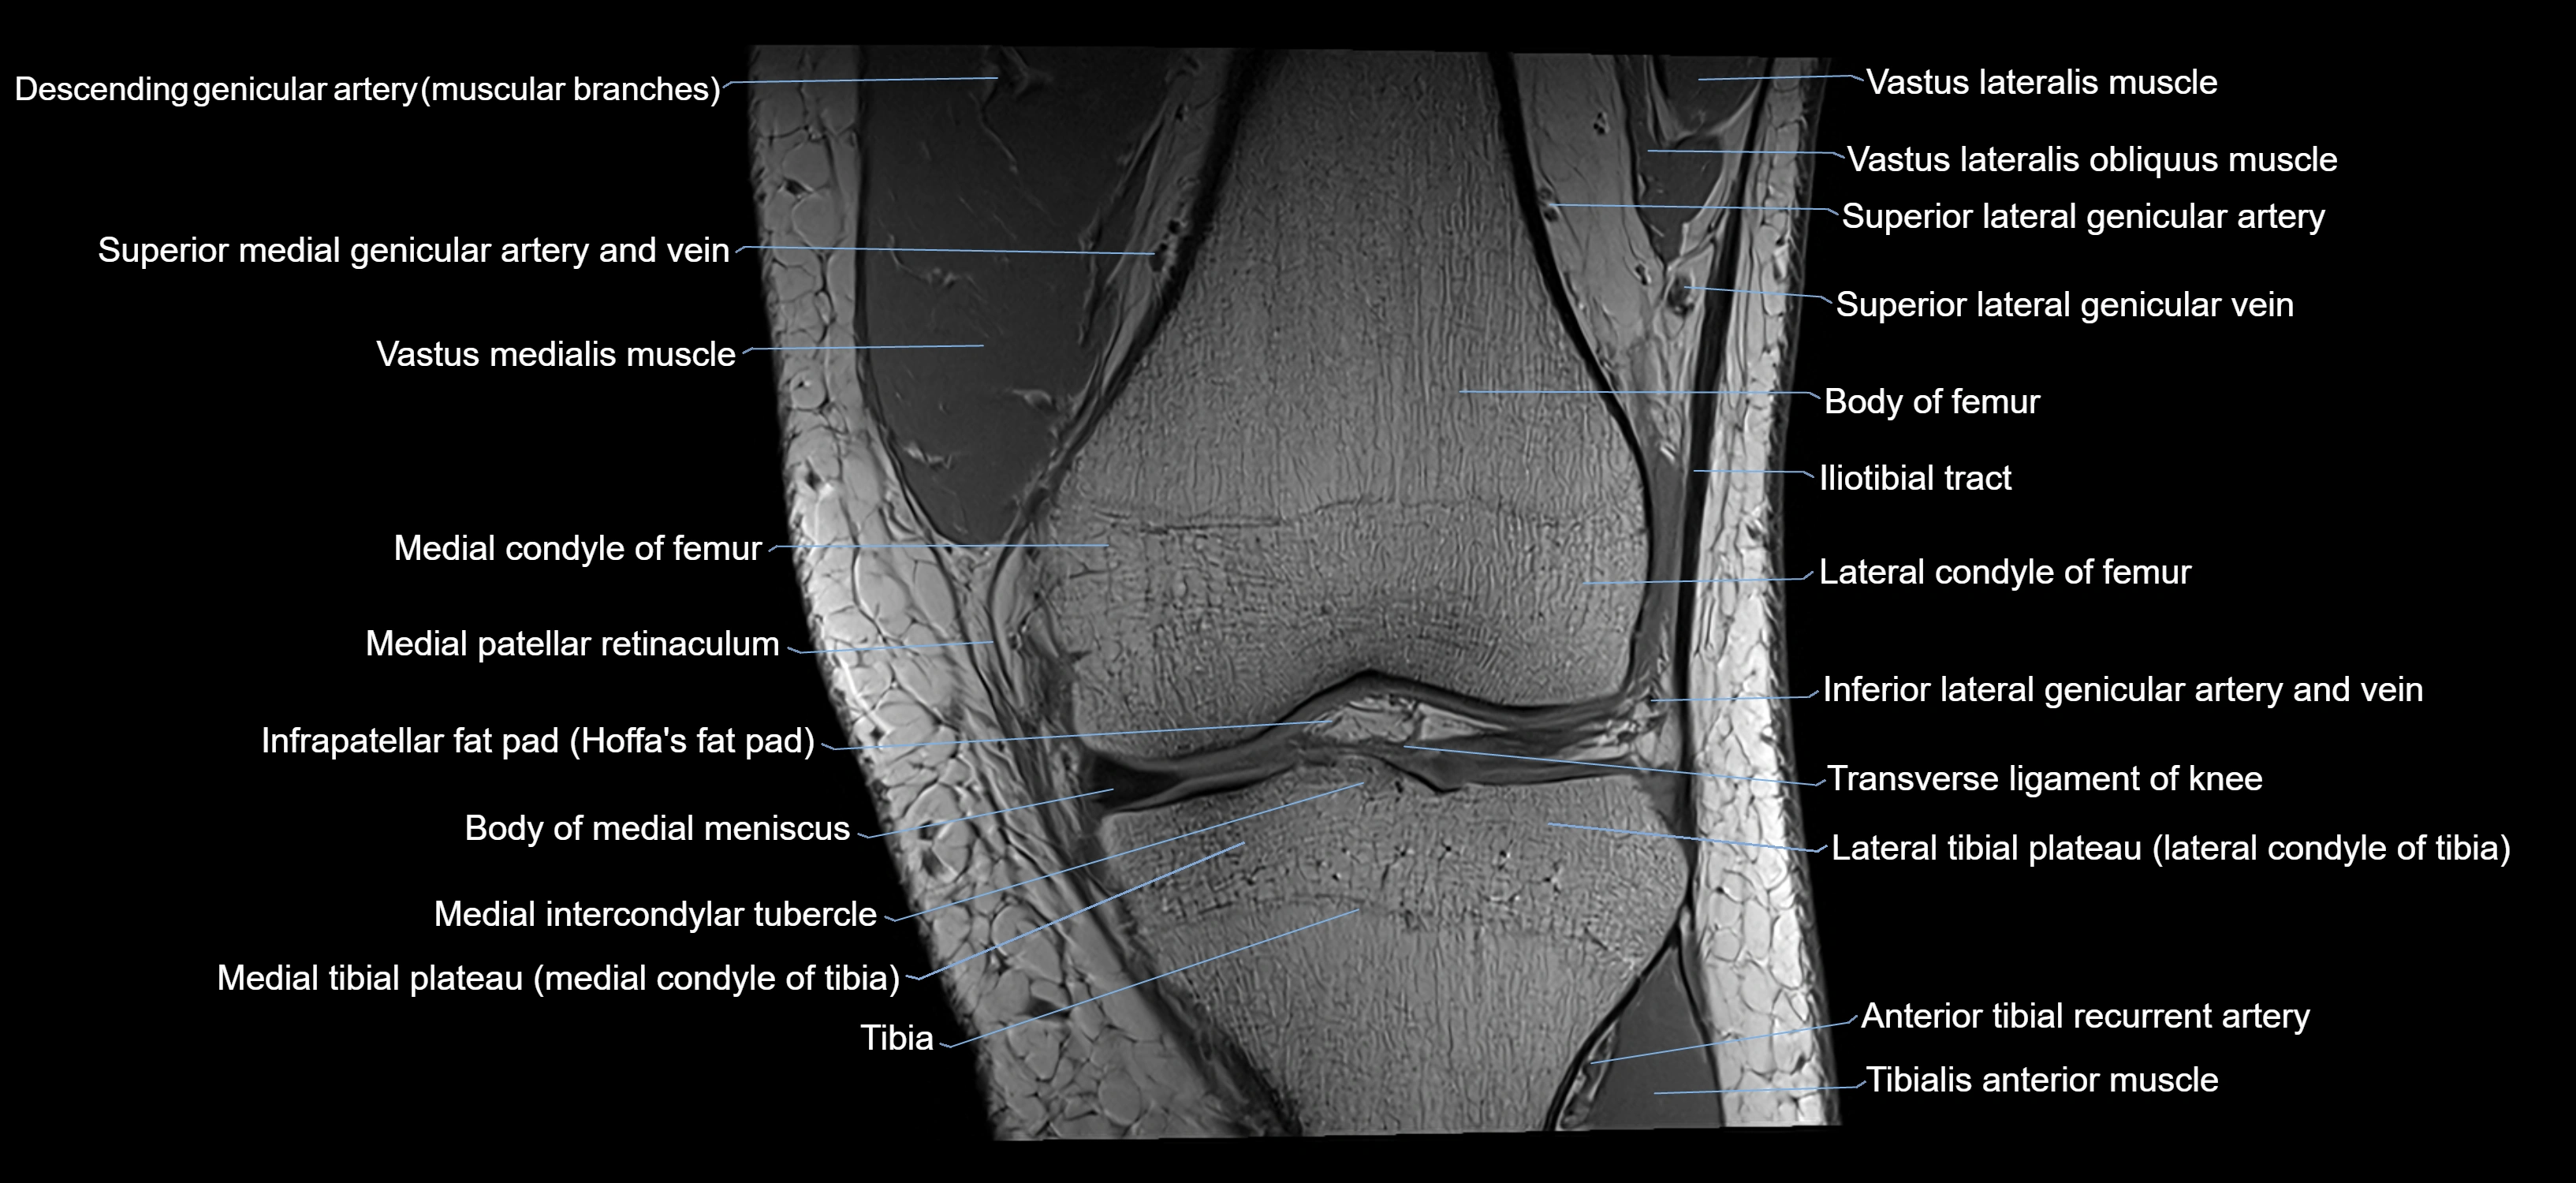

- Lateral condyle of femur

- Medial condyle of femur

- Lateral tibial plateau

- Medial tibial plateau

- Medial intercondylar tubercle

- Lateral intercondylar tubercle

- Body of medial meniscus

- Medial patellar retinaculum

- Infrapatellar fat pad

- Superior lateral genicular artery

- Superior lateral genicular vein

- Superior medial genicular artery

- Superior medial genicular vein

- Transverse ligament of knee

- Vastus lateralis muscle

- Vastus medialis muscle

- Tibialis anterior muscle